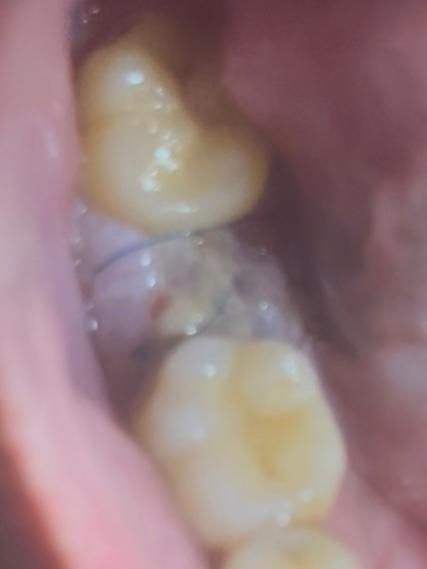

어금니 발치 혈병 관련 질문있습니다.

1. 왜 저의 혈병은 이렇게 거뭇거뭇한 것일까요? 드라이소켓 확률이 있나요? (아프거나 냄새가 나지는 않습니다.)

2. 그리고 이것이 혈병이 맞나요?

• 2번 째 사진

1. 그냥 이물질 낀겁니다

2. 혈병에서 치유를 위한 염증,육아조직으로 바뀌고 있는겁니다

1. 혈병의 경우에는 원래 약간 거뭇하게 보입니다.

2.초기에는 혈병이 나타나지만 시간이 지나면 섬유화가 진행되어 지금처럼 하얗게 보입니다.